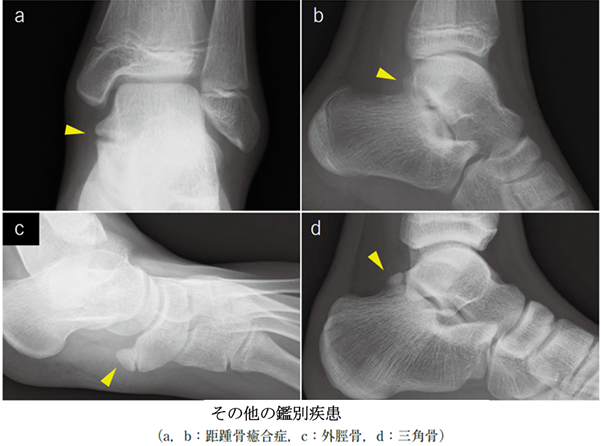

その他の鑑別疾患: 有痛性外脛骨、足根骨癒合症、三角骨障害など特有な疾患が合併していることもあります。

(図24)MB Orthop. 38(5):55—64,2025大人とこどものスポーツ外来 下肢編

【こども編】小児アスリートの足関節・足部捻挫に対する外来診療 田中 博史 より抜粋